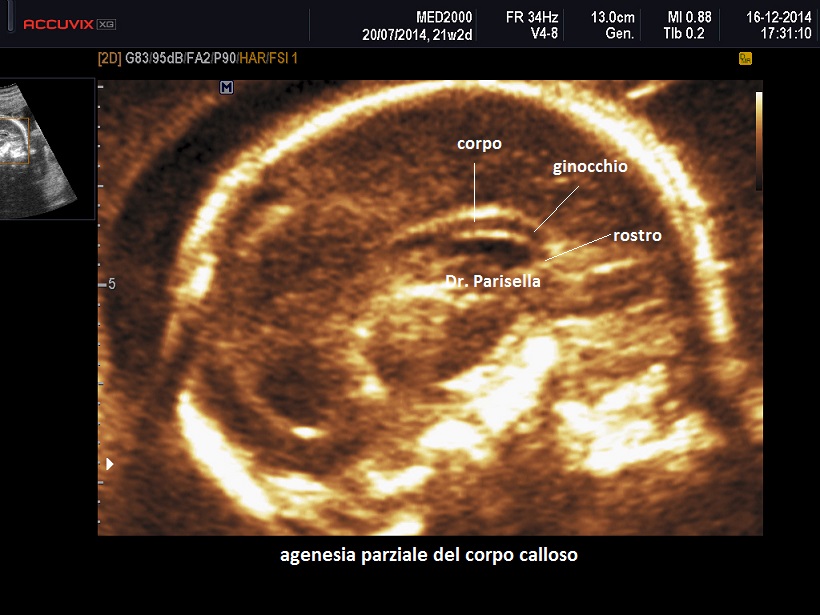

Agenesia del corpo calloso - microcefalia - bassa statura o Sindrome di Da Silva

E' caratterizzata da ipoplasia del corpo calloso, microcefalia, grave deficit cognitivo, appendici cutanee preauricolari, camptodattilia, ritardo di crescita.